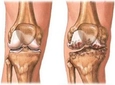

Kireçlenme, eklemlerdeki kıkırdağın dejenerasyonu sonucu oluşan ve genellikle yaşlı bireylerde görülen bir durumdur. Belirtileri arasında ağrı, şişlik ve hareket kısıtlılığı yer alır. Tanı genellikle muayene ve görüntüleme yöntemleriyle konur. Tedavi ise ilaç, fizik tedavi ve yaşam tarzı değişikliklerini içerir.

Kireçlenme, tıbbi literatürde osteoartrit olarak bilinen, eklemlerdeki kıkırdağın dejenerasyonu sonucu ortaya çıkan bir durumdur. Bu durum, yaşlanma, genetik faktörler, aşırı kullanım ve yaralanmalar gibi çeşitli etkenlerle tetiklenebilir. Kireçlenme, genellikle yaşlı bireylerde daha sık görülmesine rağmen, genç yaşlarda da çeşitli nedenlerle ortaya çıkabilir. Bu makalede, kireçlenmenin belirtileri, tanı yöntemleri ve tedavi seçenekleri ele alınacaktır. Kireçlenmenin BelirtileriKireçlenme, çeşitli belirtilerle kendini gösterebilir. Bu belirtiler hastadan hastaya değişiklik gösterebilir, ancak genel olarak aşağıdaki semptomlar yaygındır: